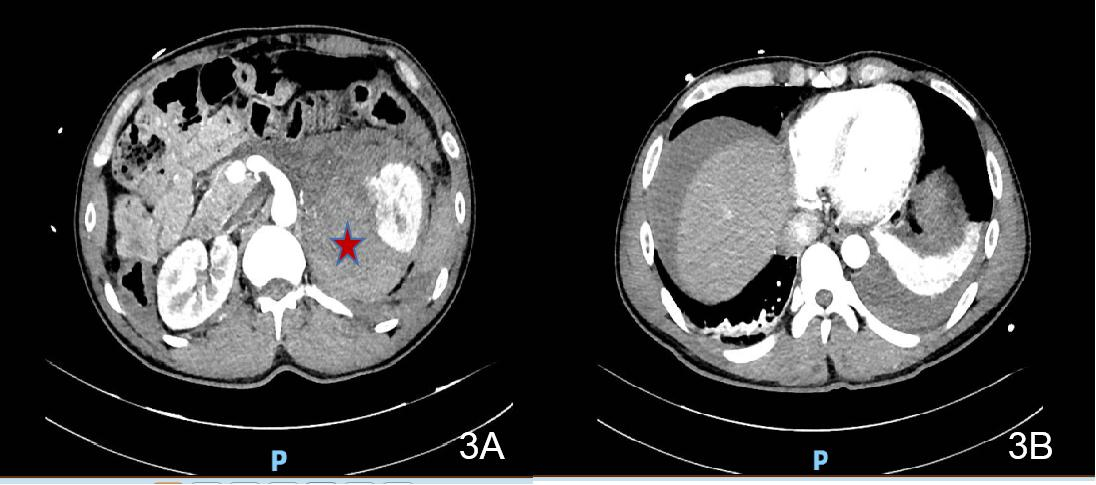

患者1初步诊断考虑急性暴发型病毒性心肌炎与儿茶酚胺心肌病鉴别,患者入院后心率快,呼吸促,满头大汗,面色苍白,双肺湿啰音,出现急性心力衰竭、肺水肿表现,病情进展迅速,随时可能出现心源性休克、恶性心律失常甚至心脏骤停等不良事件,当天转入重症医学科进一步诊治。转入后予以氧疗、控制心室率、营养心肌、抗感染、抗病毒、抗炎、护胃抑酸等支持治疗,效果欠佳,有ECMO辅助指征。征得患者及家属同意,于2017-10-01凌晨行清醒状态局麻下VA-ECMO治疗,使用右侧股动静脉切开置管。使用VA-ECMO模式,初始转速3 000 r/min,血流量3.0 L/min左右,气流量3.0 L/min,氧浓度100%,患者气促逐步缓解,心率90次/min,血压115/82 mmHg,SPO2 100%,尿量约100 mL/h。术前肝素首剂为50 mg,术后维持量为4~6 mg/h,APTT 43.8~70.3 s,ACT 130~168 s,全身各部位无明显出血,膜肺无血栓形成,在ECMO支持期间,同时予抗感染、抗病毒(阿昔洛韦)、人免疫球蛋白、艾司洛尔控制心室率(后过渡至酒石酸美托洛尔片)、控制血压等治疗。2017-10-02心脏彩超示EF下降至16%,2017-10-04将EF恢复至48%,撤离VA-ECMO。2017-10-06心脏彩超:左室心尖运动稍减弱,主动脉瓣返流(轻),二、三尖瓣返流(轻),左室射血分数57%,舒张功能稍减退。2017-10-10行冠脉造影未见明显异常。患者病情好转出院。2017-11-20返院复诊,查腹部CT发现右侧肾上腺区肿块,考虑嗜铬细胞瘤(见图 1),予服用“酚苄明”血压控制良好。2017-12-14复查心脏彩超提示:二、三尖瓣返流(轻度),左室收缩、舒张功能正常,EF 70%,肺动脉压正常(25 mmHg)。2017-12-15行择期手术治疗,病理结果符合嗜铬细胞瘤,术后患者血压恢复正常。患者最后诊断“嗜铬细胞瘤、儿茶酚胺心肌病”。

图 1 2017-11-20患者1腹部CT(右侧肾上腺区肿块)